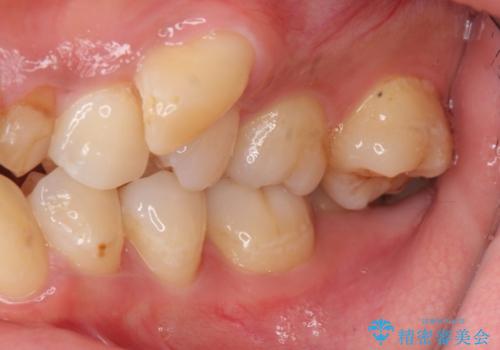

乳歯が残存しており、また左上の犬歯もずれて生えてきていました。

右上の前歯も細長い特殊な形をしていました。(矮小歯といいます)

左上の奥歯はすれ違っていたためそのかみ合わせも整えています。